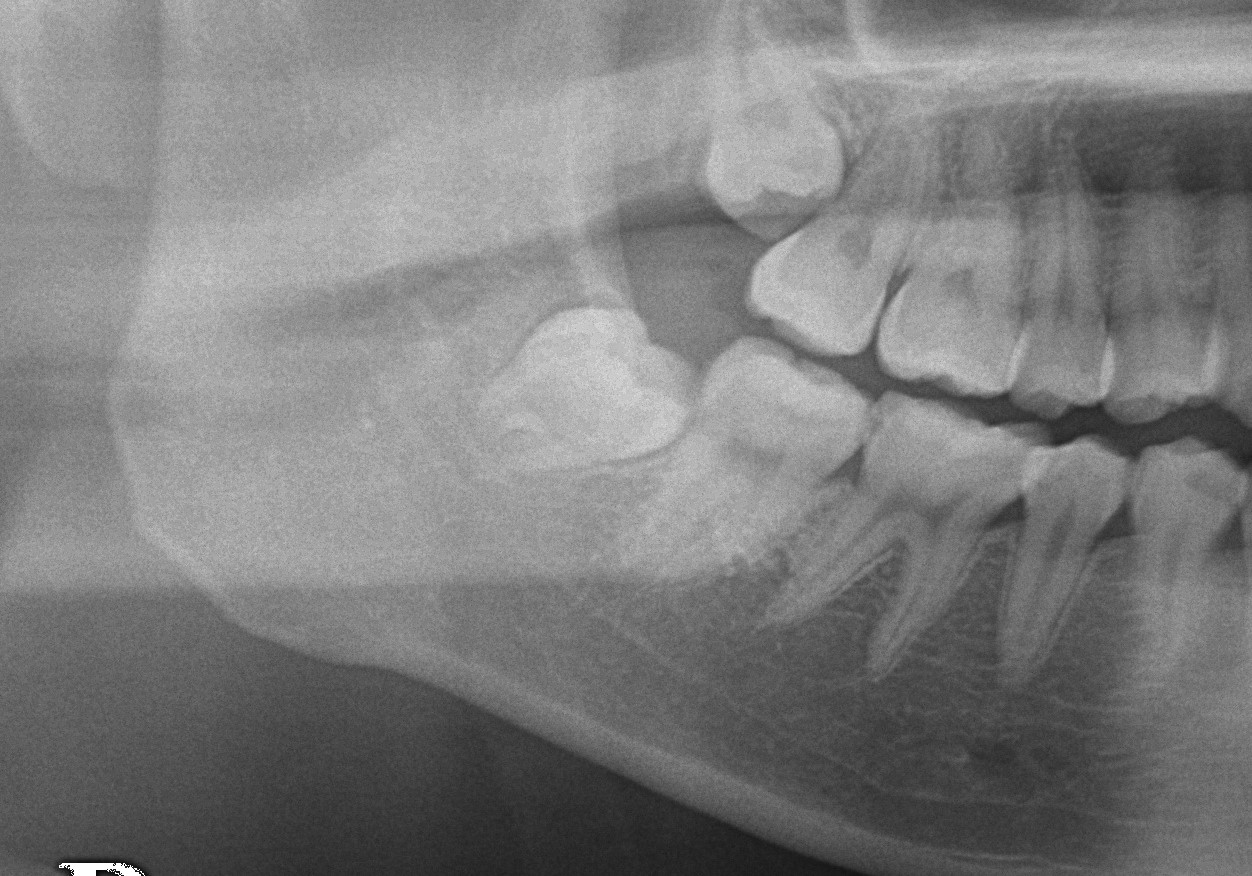

今日の抜歯(レントゲン付き)

今日は右下8の抜歯を希望されて来院された患者様の抜歯を行いました。手術時間は10分でした。患者さん曰く大学病院に紹介されたけど予約が取れずにいたところ当院をネットで見つけたそうです。 初診時に説明をおこないその場で抜歯を […]